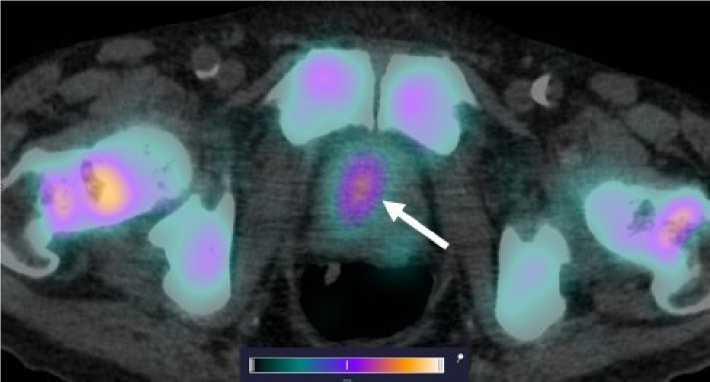

У 4 пациентов из обследованных в анамнезе было проведено радикальное лечение первичной опухоли в объеме либо простатэктомии (n = 2), либо дистанционной лучевой терапии (n = 2), по результатам динамического наблюдения данных за рецидив заболевания, продолженный рост опухоли получено не было, накопления [99mTc]Tc-HYNIC-PSMA в ложе предстательной железы (ПЖ) также не наблюдалось. У 6 пациентов ПЖ не была удалена, у одного из этих пациентов начата антиандрогенная терапия, еще у одного пациента диагностировано прогрессирование заболевания после 2 линии терапии — у всех больных отмечалось очаговое накопление РФЛП в предстательной железе (рис. 3). Для количественной оценки интенсивности накопления индикатора использовался показатель стандартизированного уровня накопления (SUV, the standardized uptake value). Средние значения SUVmax в проекции предстательной железы составили 6,575 ± 2,307.

Рис. 3. ОФЭКТ/КТ изображение больного раком предстательной железы через 2 чпосле инъекции [99mTc]Tc-HYNIC-PSMA. На ОФЭКТ-КТ-изображении cтрелкой отмечено накопление РФЛП в предстательной железе (SUVmax 10,68). В костных структурах на уровне сканирования также визуализируется накопление РФЛП

Fig. 3. SPECT/CT image of a prostate cancer patient 2 hours after injection of [99mTc]Tc-HYNIC-PSMA. Accumulation of radiopharmaceutical in the prostate is indicated by the arrow (SUVmax 10.68). Аccumulation of radiopharmaceutical is also visualized in bone structures at the scanning level